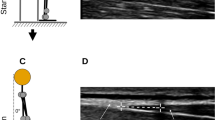

The TLF shear modulus was measured at the third and fourth lumbar vertebra levels (L3 and L4).The location of the L4 spinous process was identified by a body surface marker and reconfirmed by B-mode ultrasound. Then, the position of the L3 spines is determined by B-mode ultrasound. The longitudinal center of the probe at horizontally 2 cm from the right side of the L2–3 and the L3–4 midline (Fig. 1)5,15,16. These gauge points were marked with an oil-based pen. The marker of each experiment was cleaned at the end of the experiment.

Illustration of the two postures (a) sitting; (b) sitting-forward 60°, and setting out plan of ultrasound transducer (c).

All subjects performed experiments in a given posture: sitting, sitting-forward 60° (Fig. 1). In all postures, subjects are required to keep their heads in a neutral posturewith their upper limbs at their sides. In sitting posture, the subjects are required to keep their feet shoulder-width apart and both feet flat on the floor. Their legs are perpendicular to the ground, and their knees bent at 90°.We used a self-made sloping panel to keep the subjects' upper body at 0° and 60° of forward tilt.